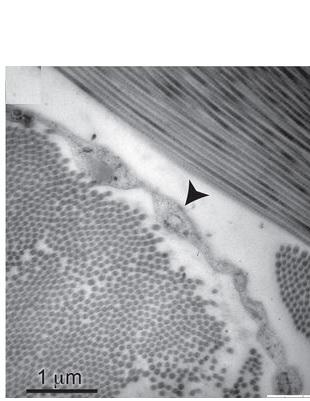

Le tissu s’avère être « un espace ouvert, rempli de fluide, soutenu par un treillis constitué de faisceaux épais de collagène, une protéine qui agit comme une sorte d'échafaudage autour des poches de liquide. Ces faisceaux de collagène sont doublés du côté ne faisant pas face au fluide par une couche de cellules plates. Les chercheurs observent enfin des structures similaires dans le tissu entourant la peau, le tube digestif, la vessie, les voies respiratoires et les vaisseaux sanguins.

La découverte actuelle réside donc dans cette structure « en forme de filet » entourant les espaces remplis de liquide dans le tissu. Le liquide situé à l'intérieur de cette structure semble s'écouler dans le système lymphatique. Par ailleurs, les chercheurs observent la présence de cellules cancéreuses dans certains de ces tissus et émettent l’hypothèse que les espaces remplis de liquide de l'interstitium pourraient être l'une des voies par lesquelles les cellules cancéreuses se propagent et cela jusqu’aux ganglions lymphatiques. Le cancer peut en effet se propager à travers le système lymphatique.